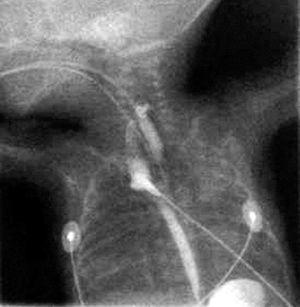

Se realizó un esofagograma que mostró la presencia de una perforación esofágica en la unión proximal del esófago con la faringe, con formación de un seudodivertículo cuyo extremo distal se situó aproximadamente a la altura de la cuarta vértebra dorsal (fig. 2).

Figura 2. Esofagograma con localización ectópica del contraste en la unión proximal del esófago con la faringe.